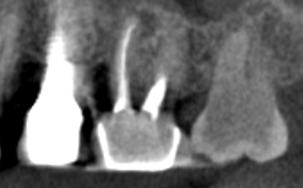

CBCT Scans provide a 3D dental image, while traditional X-rays are only a 2-dimensional picture of the mouth. This means that with traditional X-rays alone, it is very difficult to diagnose non-painful lesions like dental abscesses that are within the jaw bone.

Here are some examples of photos of bone lesions

Patient “A ”Xray of a root canal tooth #14 CBCT Scan of same tooth #14, notice the lesion on the bone at the tip of the left root Notice root canal #13 on xrays CBCT Scan on same tooth #13, there is a lesion at the tip of the root causing sinus membrane inflammation. Patient “C” xray tooth #14 Patient “C” CBCT Scan tooth #14, bone lesion affects both roots. Upland Lighthouse Dentistry, a renowned family dentist in Upland, offers cone beam CBCT scan technology for comprehensive dental care. Our expert dentist utilize this advanced 3D imaging technique to obtain precise details of dental structures, soft tissues, and nerve paths, enhancing our diagnostic accuracy and treatment planning. Contact Upland Lighthouse Dentistry today!